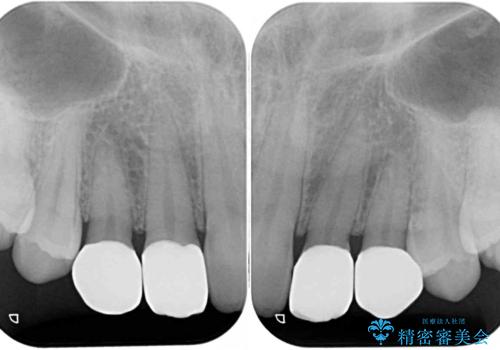

- 前歯の奇形や欠損、乳歯残存などによる審美障害を気にして来院された患者様です。

正中の隙間は矯正治療により閉じ、左右の4歯はオールセラミッククラウンにて補綴することとしました。

前歯2本もセラミッククラウンを装着することで隙間を閉じる治療方法もあるかと思いますが、健全な歯を削る必要は全くなく、矯正治療で対応することが望ましい治療であると考えます。